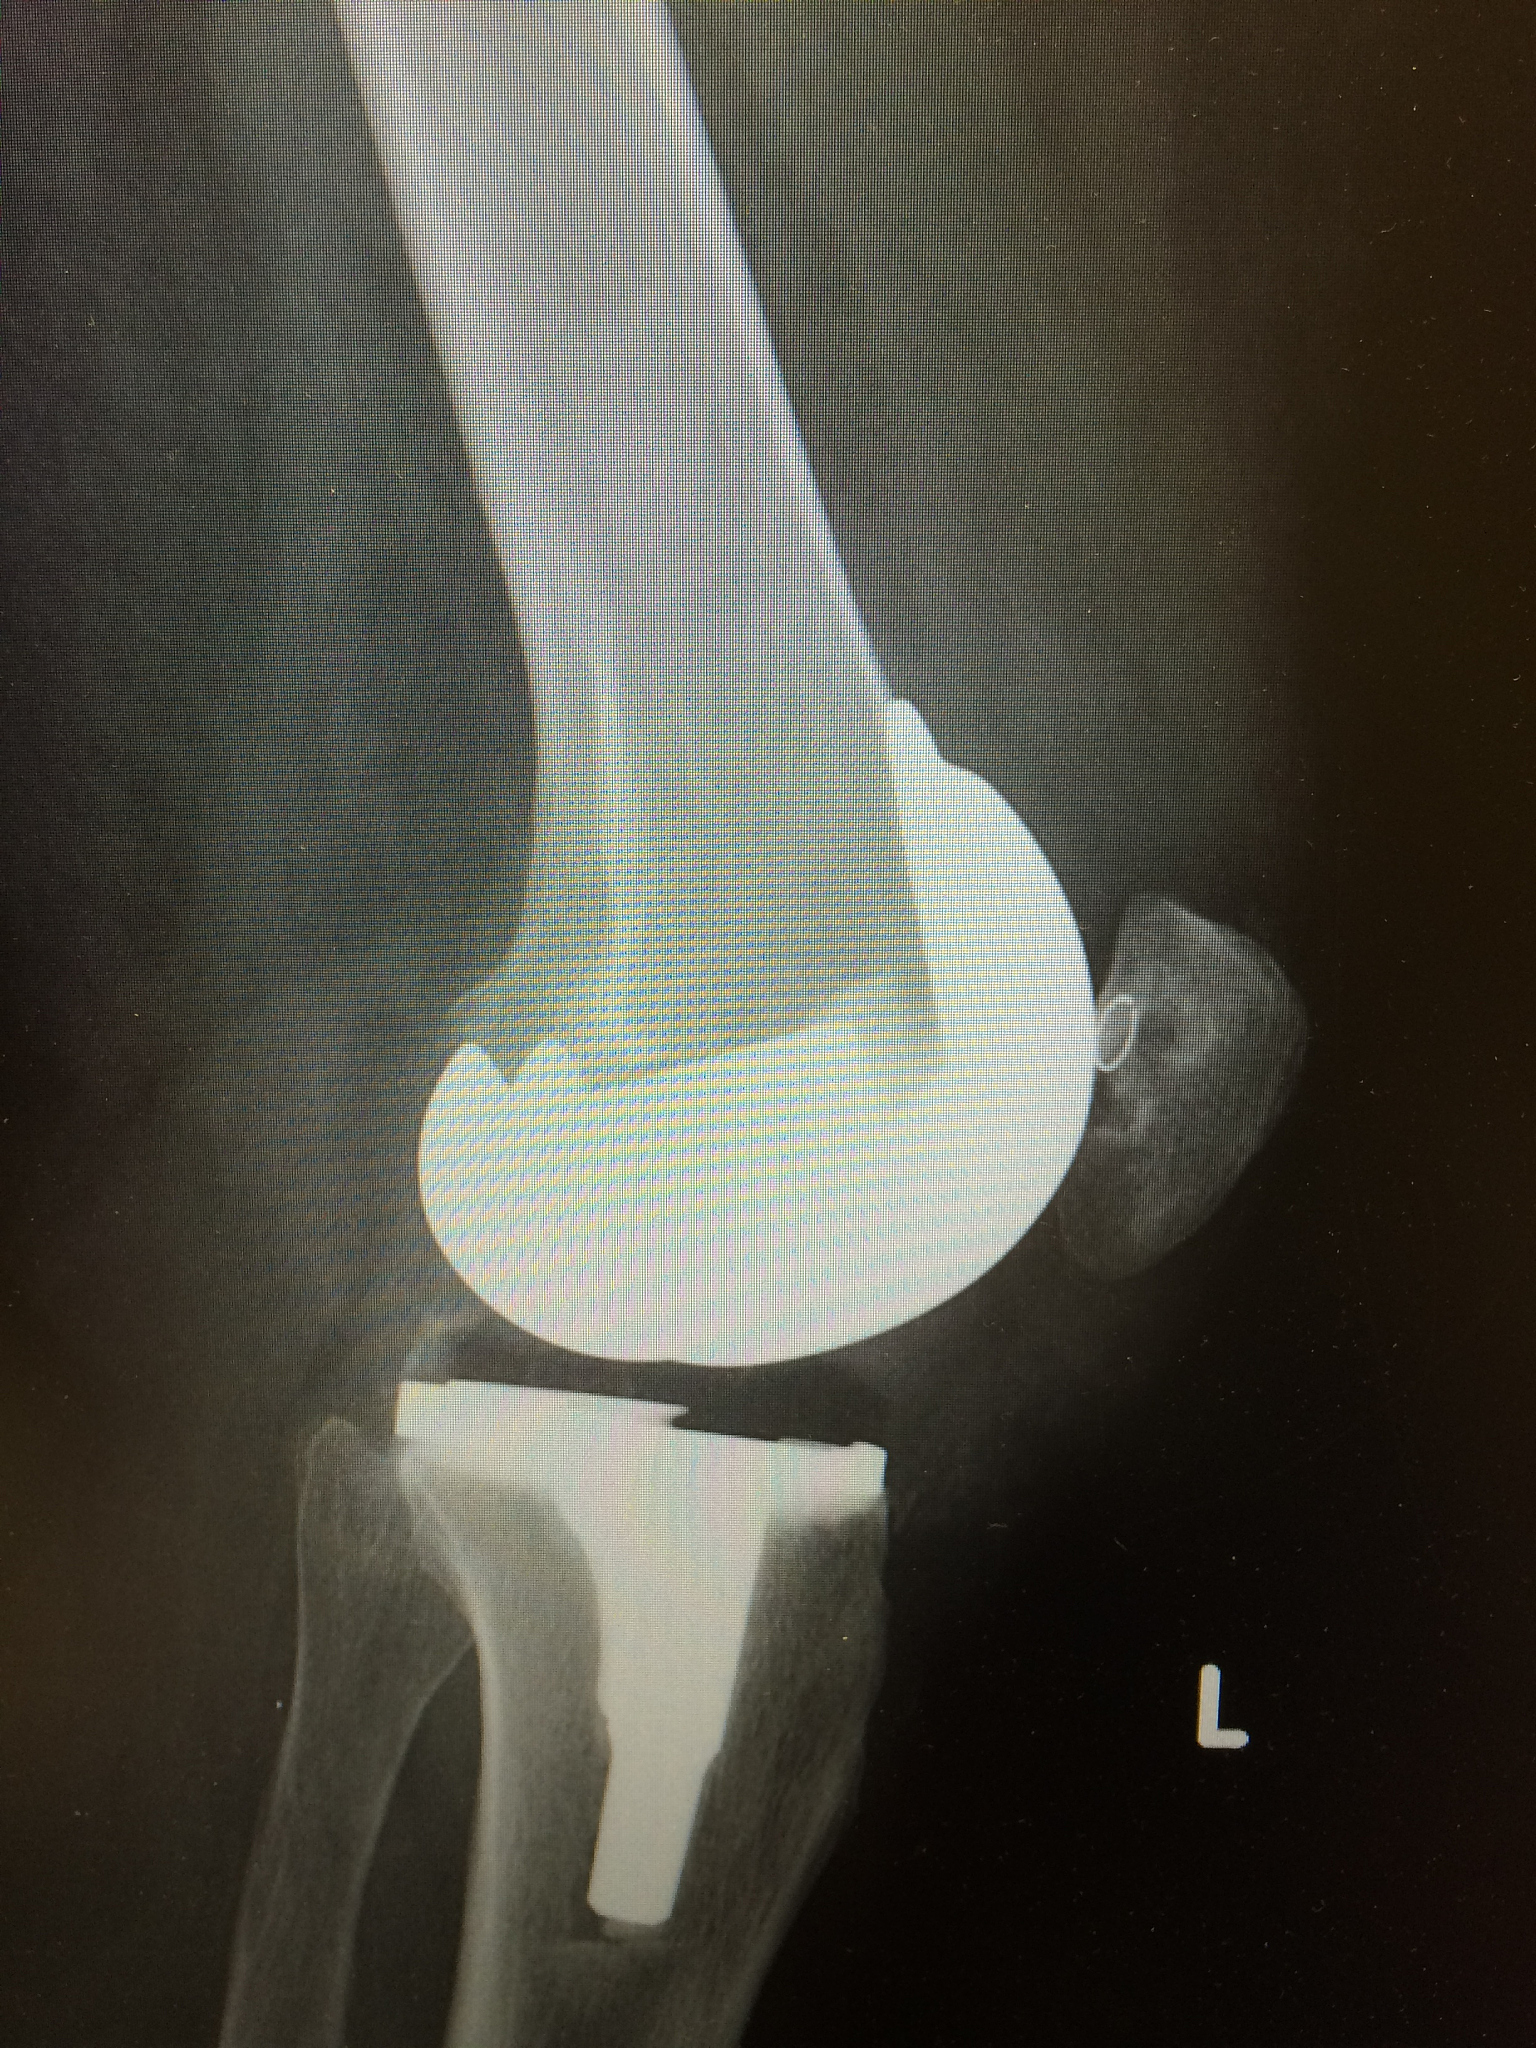

其次,Skou等人(2015)的研究揭示了全膝关节置换手术在膝关节骨关节炎治疗中的重要作用。他们发现,对于严重病情的患者,全膝关节置换手术可以提供更好的疼痛缓解和功能改善。然而,个体化治疗算法模型强调了手术治疗应该基于患者的个体特征和病情综合考虑,避免对所有患者都进行手术的风险。

然而,Skou等人的研究表明,对于膝关节骨关节炎患者来说,全膝关节置换手术仍然是一种有效的治疗方法。他们认为,个性化治疗算法应该综合考虑患者的特征和病情,以制定最佳的手术治疗方案。